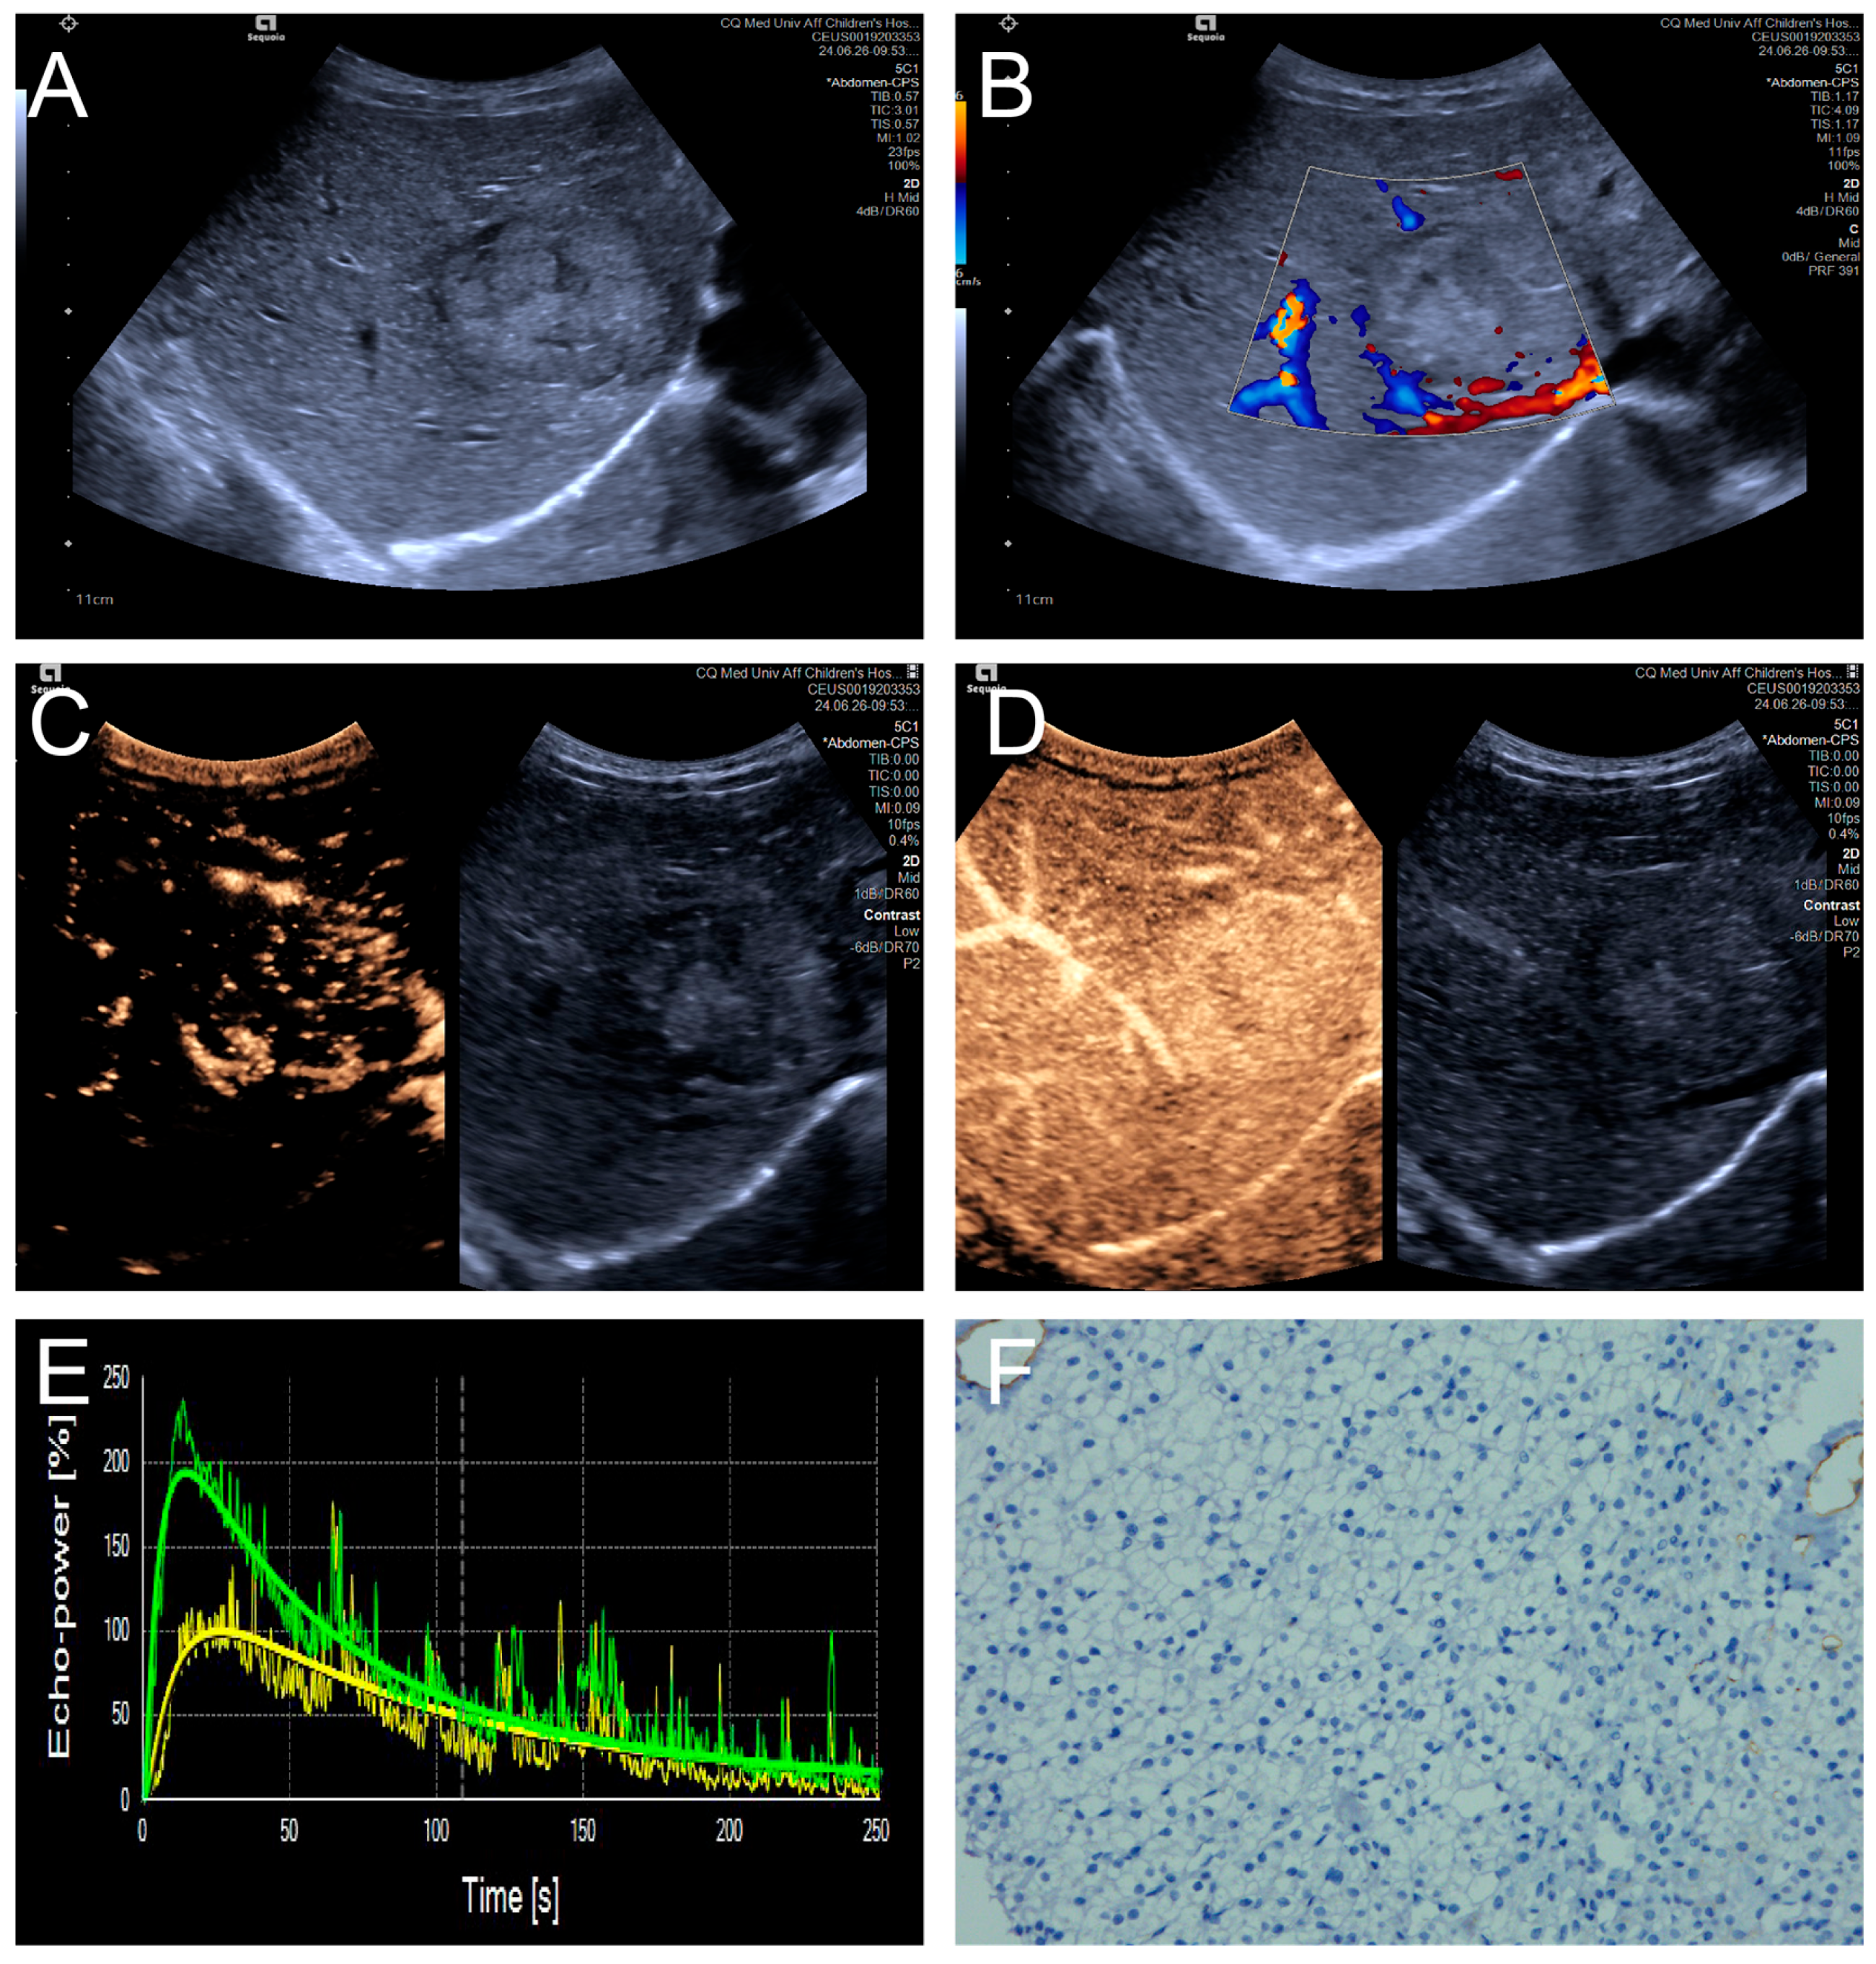

Figure 4.

(A–F) A male patient aged 10 years and 6 months with HB and high MVD. (A) The imaging revealed a lesion with unclear margins and hyperechoic echogenicity in the liver’s left lobe; (B) During the enhancement phase, CDFI revealed abundant vascular signals within the tumor tissue, classified as grade III by Adler; (C,D) The CEUS exhibited non-uniform enhancement progressing from periphery to center, with non-enhancing regions (triangles) within the lesion and peripheral penetrating vessels (arrows); (E) TIC curves showed contrast enhancement of the lesion (green) and perfusion of the adjacent liver parenchyma (yellow). Jagged lines indicated raw signal data, and smooth lines indicated the fitted curves; (F) The biopsy specimen’s cytological immunohistochemical staining revealed dense microvessels (CD34 staining × 200), and the MVD measured 42 lines/HPF.